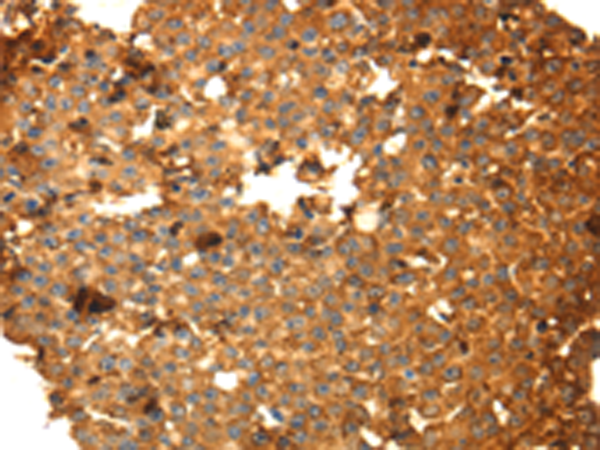

IHC positive control: |

Human breast cancer |

IHC Recommend dilution: |

50-200 |